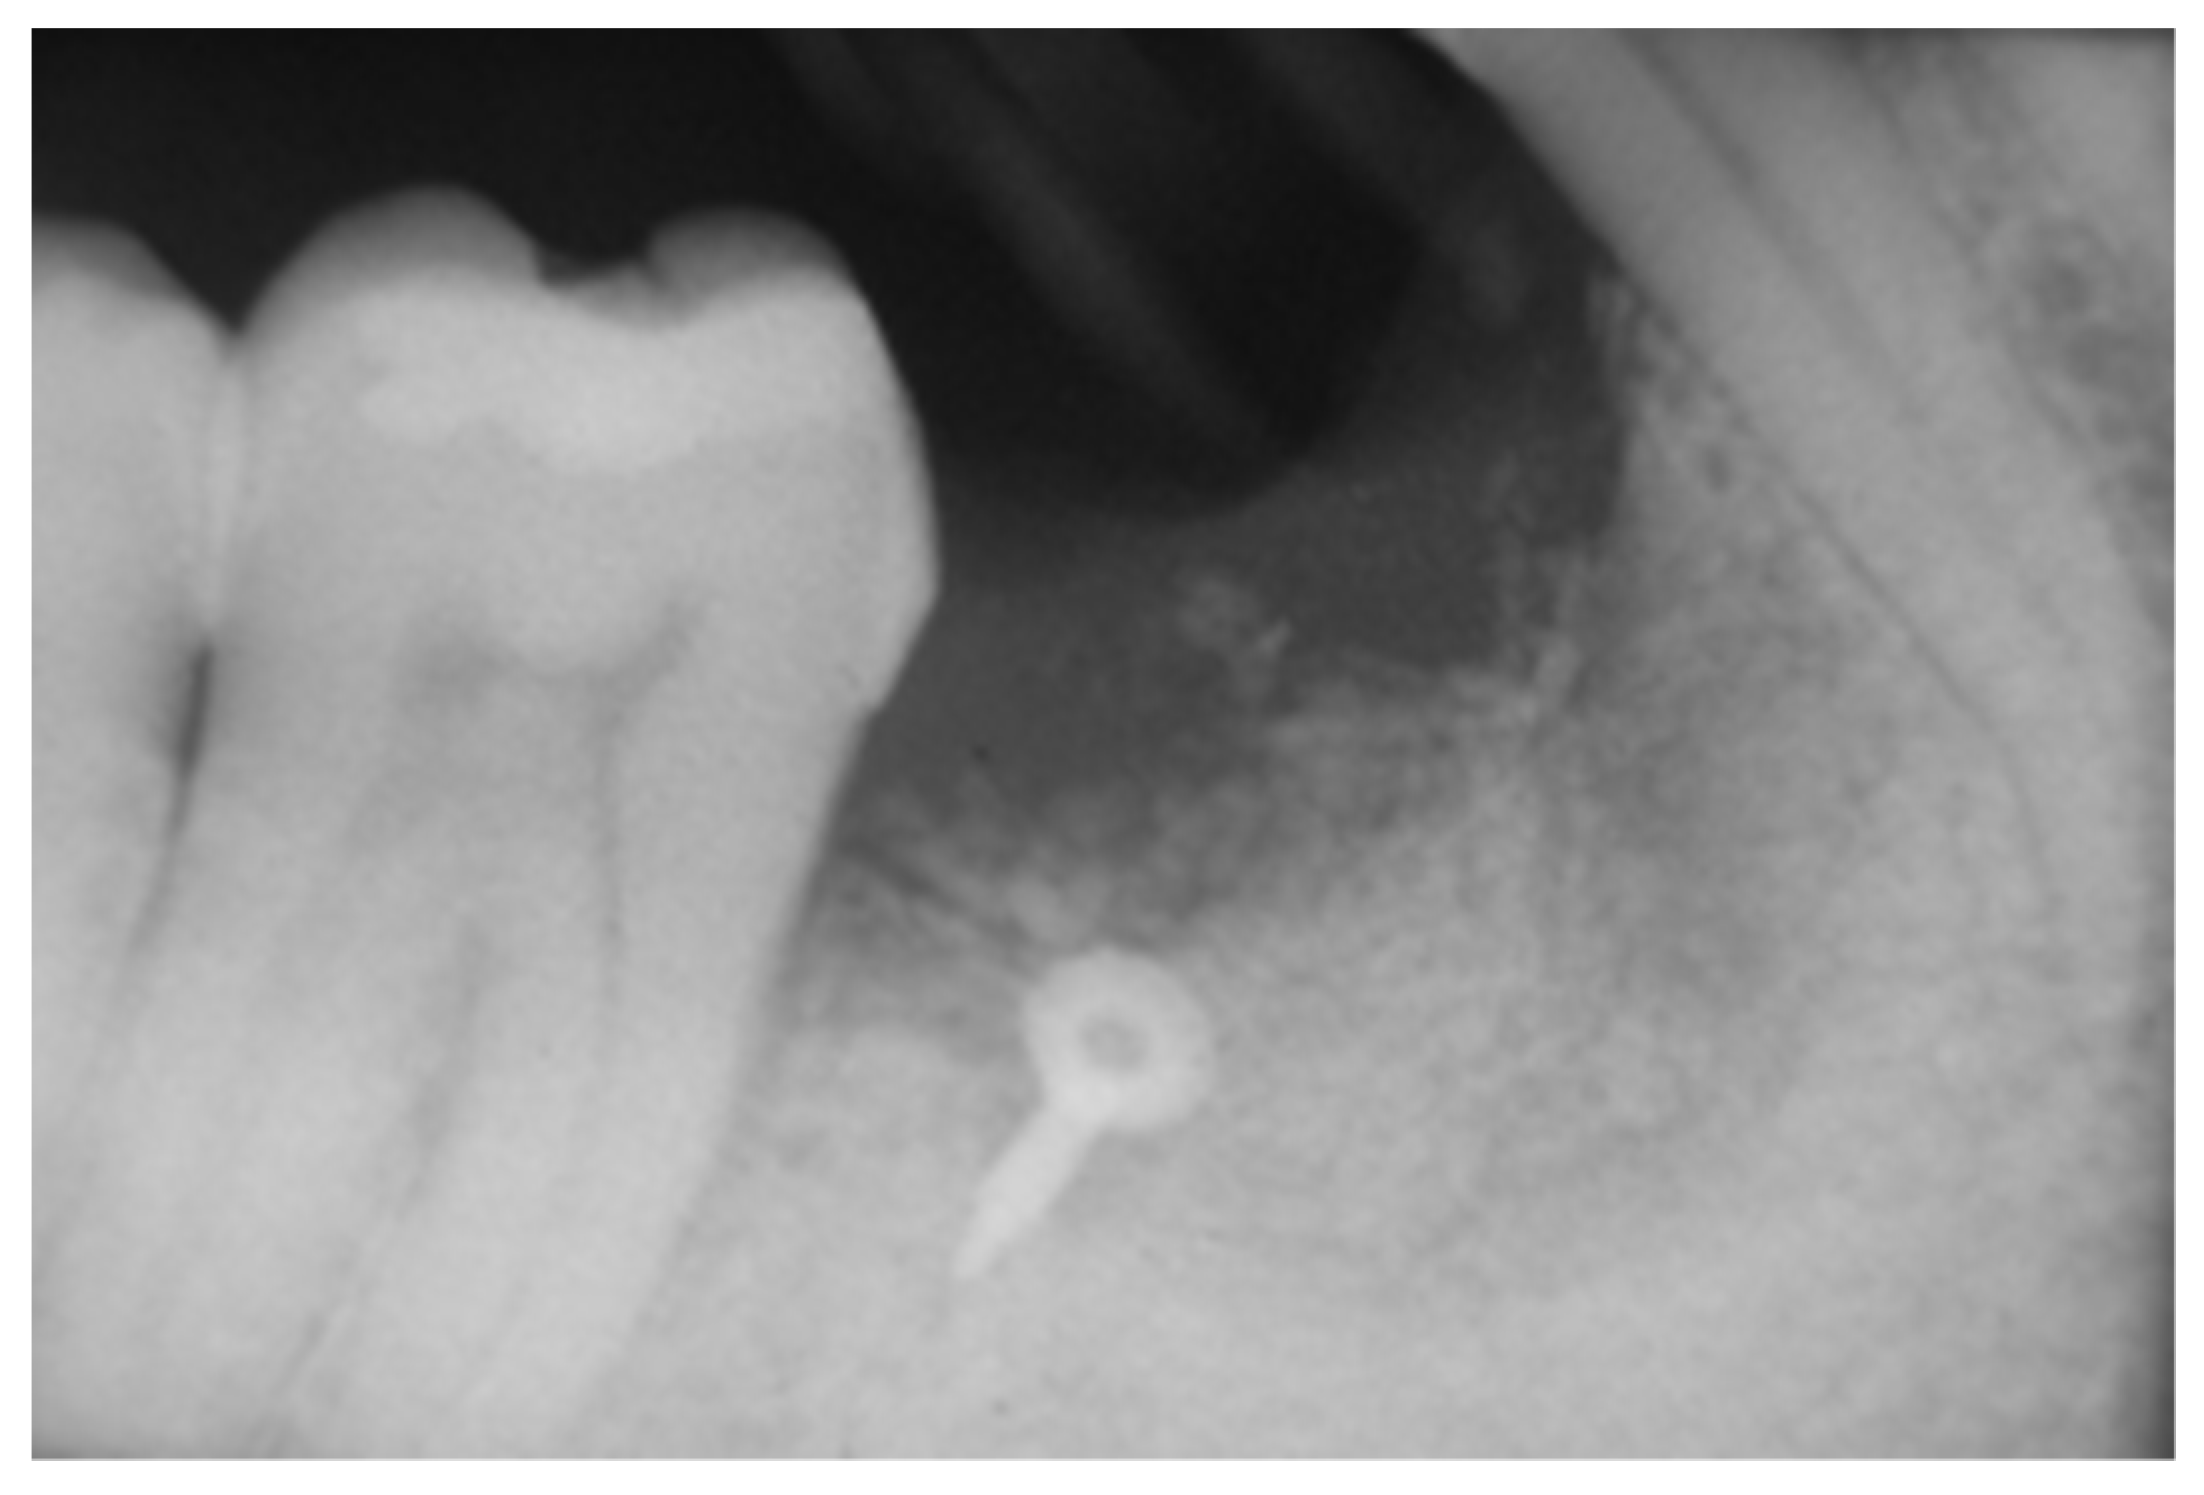

2.3. Peri-Implant Bone Levels Assessment